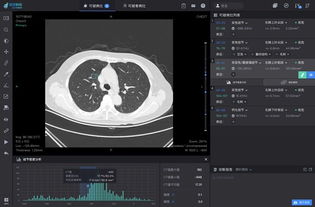

主控台:负责图像参数的设置、图像显示和存储等功能。

胸部诊断:如肺炎、肺结核、肺癌等。

图像质量:通过改进X射线源和探测器技术,CT系统的图像质量得到了显著提高。

人工智能辅助诊断:利用人工智能技术,提高CT图像的解读准确性和效率。